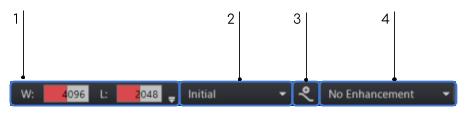

Az eRAD PACS támogatja az ablak szélességének és közepének előzetes beállításait. Az előzetes beállítások lehetővé teszik egy vagy több beállítás csoportosítását egy specifikus funkcióra. Ezután ezek a beállítások használhatók, ha kiválasztja őket a listából. Előre beállított ablak és szint esetén létrehozhat modalitás-specifikus ablak-/szintpárokat, és alkalmazhatja azokat a jelenlegi képhez úgy, hogy kiválasztja a címkét a listából. Az ablakok és szintértékek előre beállított listája nyilvántartja az összes mentett ablakolási beállítást egy specifikus modalitás típushoz. Az előre beállított ablakolási lista az Ablakolás eszköztárban jelenik meg. Az előre beállított értékek listája a legördíthető menüben található. Néhány alapértelmezett érték megtalálható az alapértelmezett ablakolási listában.

Ablakolás értékek

Az előre meghatározott beállítások az Ablakolás eszköztár Ablakolás lenyíló menüjében érhetők el a kiválasztott képhez.

Az ablakolás értékei kétféleképpen módosíthatók a numerikus érték mezőben:

Csúszka – Kattintson a mezőre, és húzza felfelé az érték növeléséhez, és lefelé annak csökkentéséhez

Explicit numerikus meghatározás – Válassza ki azt a helyet, ahol az érték van, és adja meg a kívánt számértéket

Az Ablakolás eszköztár bal oldali végén lévő mezőértékektől jobbra lévő kis nyíl egy lenyíló menü. Hisztogram megjelenítéséhez válassza ki a jobb oldali  lefelé mutató nyilat.